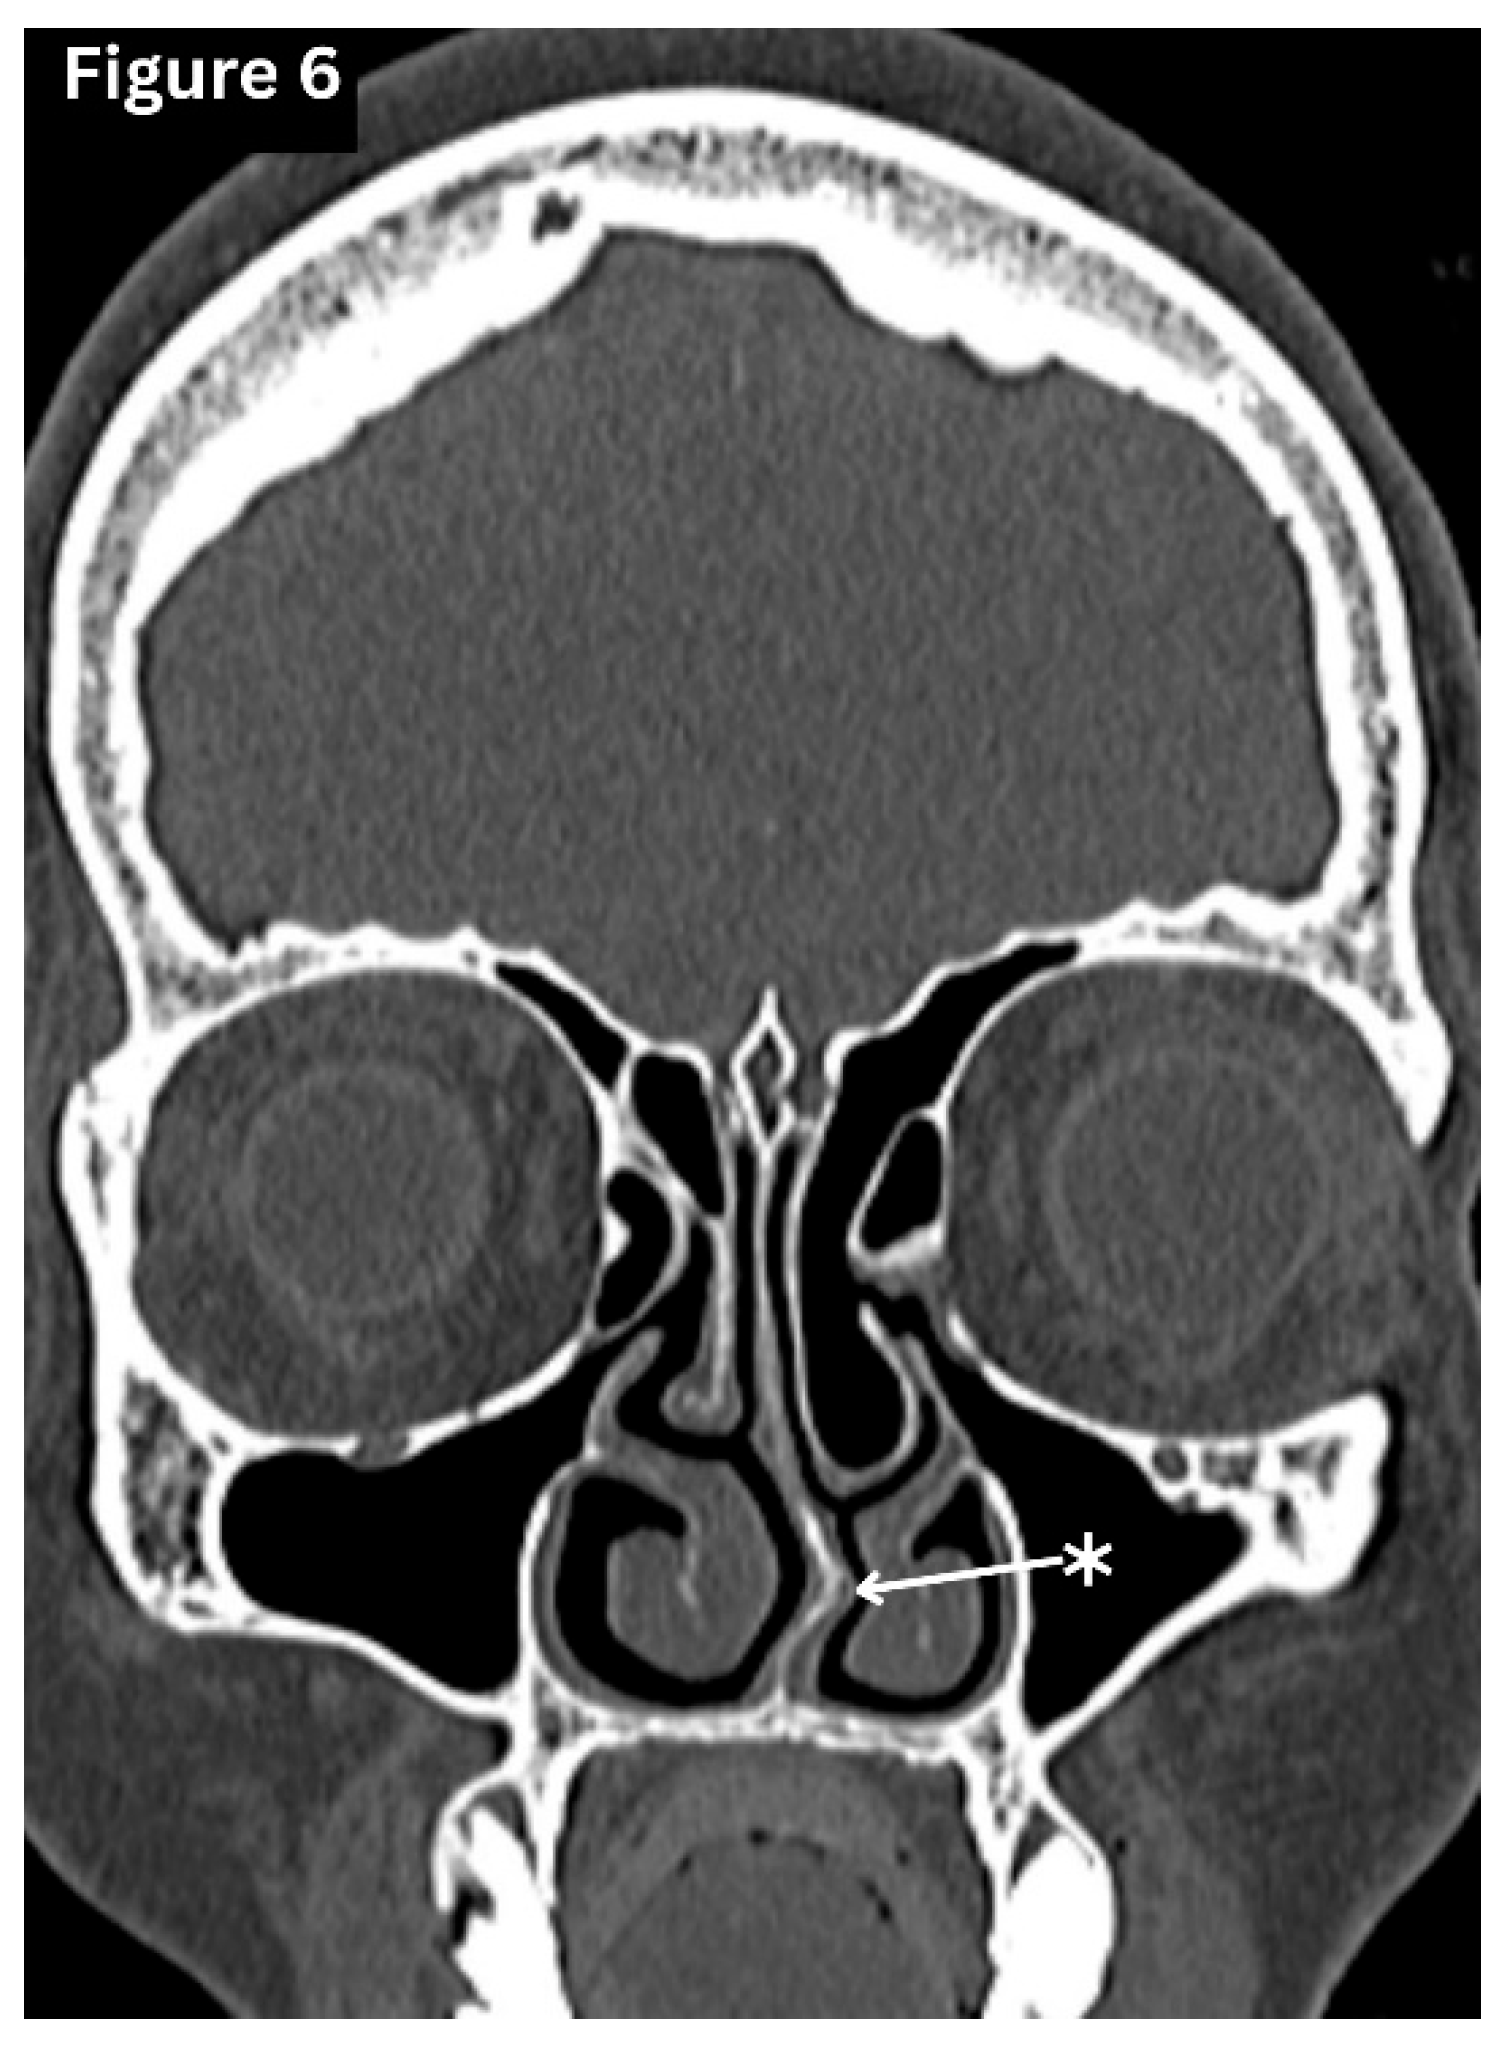

Deviated Nasal Septum (DNS)

This is defined as the displacement of the nasal septum from the midline, resulting in an increased angle of the septum detected on a coronal CT scan or nasal endoscopy. (Figure 6) A significantly deviated septum reduces airflow and alters mucociliary clearance. It may narrow the middle meatus, thereby increasing the risk of chronic rhinosinusitis in maxillary or ethmoidal sinuses [11].

Figure 6. Coronal CT image shows mild nasal septal deviation towards the left side with a bony spur.